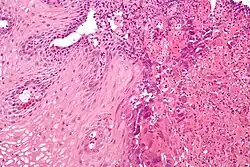

| An esophageal ulcer visualized by esophagoscopy: the reddened area at 10 o'clock on the surface of the mucosa. | |